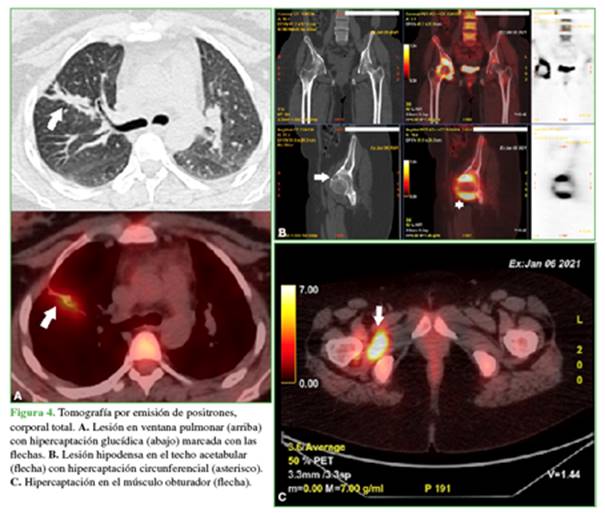

La evaluación también incluyó una tomografía por emisión de positrones (Figura 4) que mostró una lesión en el lóbulo pulmonar derecho superior, con tractos fibrosos y bronquiectasias asociadas con hipermetabolismo glucídico (SUVmáx. 4,2). Además, se visualizó una lesión osteolítica con disrupción de la cortical e intenso hipermetabolismo glucídico en el sector anterosuperior del acetábulo derecho (SUVmáx. 14,2). Se acompañaba de hipermetabolismo de morfología anular rodeando la cabeza femoral, que mantenía su esfericidad, lo que sugiere una patología capsular. En el músculo obturador externo, entre el isquion y el macizo trocantérico, se observó una imagen hipodensa hipermetabólica de 30 mm (SUVmáx 11).